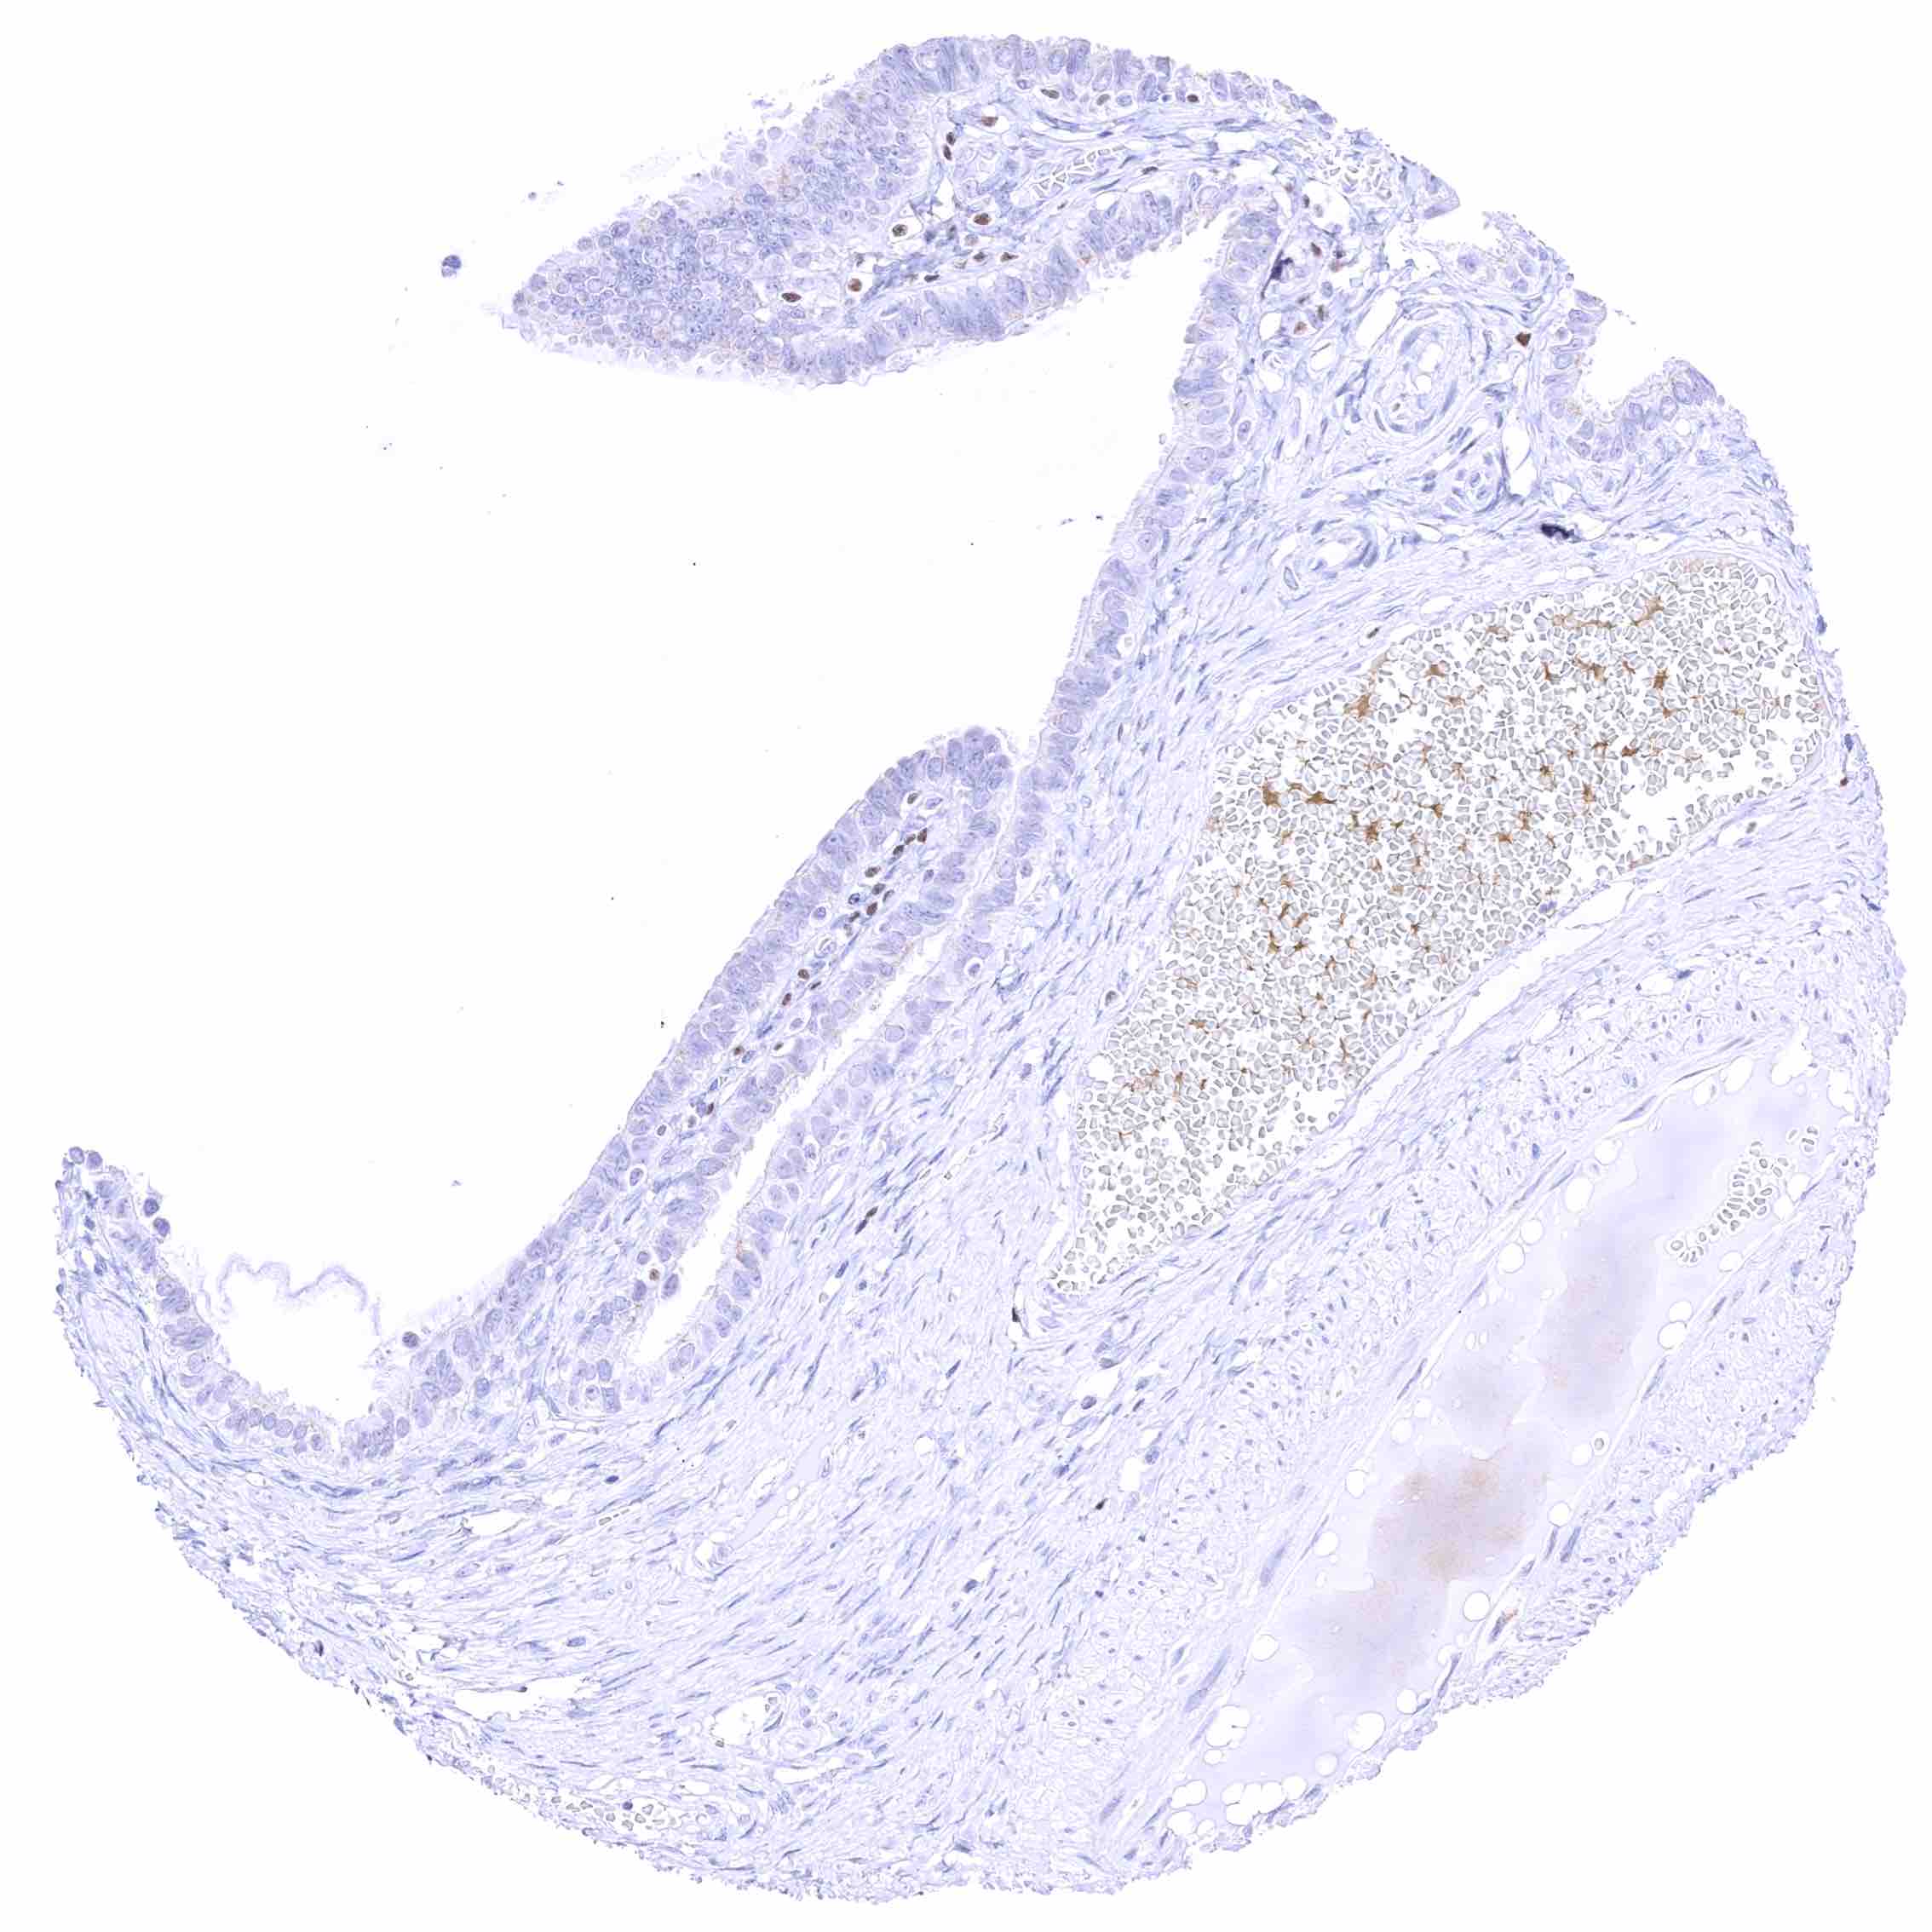

Skin, anal canal – Weak to moderate nuclear GATA3 staining of squamous epithelial cells. The staining predominates in the lower half of the epidermis.